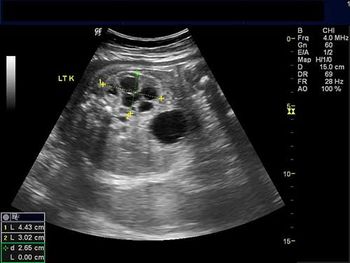

Challenge your diagnostic skills with these images of the left hemipelvis of a young woman.

Challenge your diagnostic skills with these images of fetal kidneys.